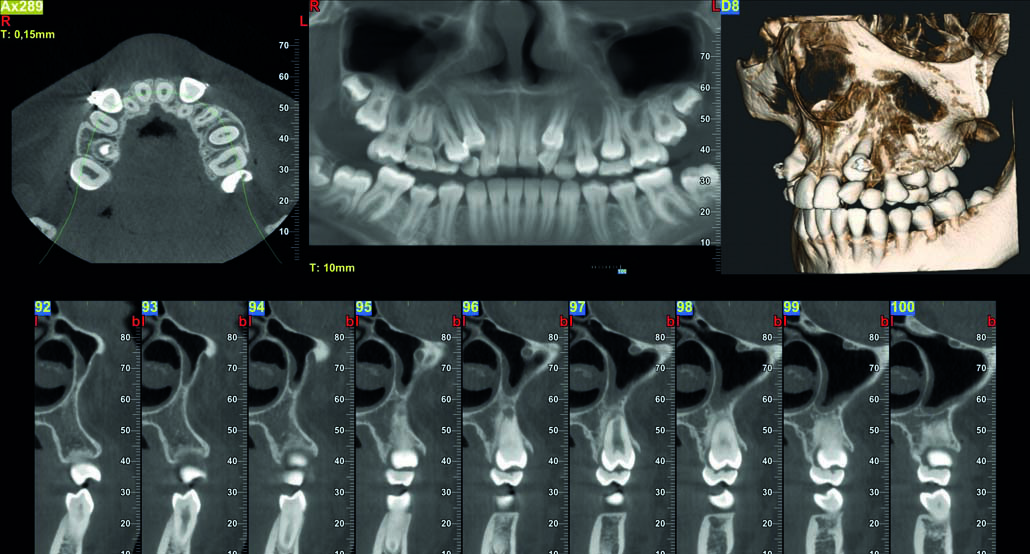

NewTom rendgeni – precizna dijagnostika u Vašoj ordinaciji

NewTom ekstraoralni rendgenski uređaji (OPG i CBCT) predstavljaju zlatni standard u stomatološkoj dijagnostici. Njihova preciznost, brzina i jednostavnost korištenja omogućuju brzo i pouzdano dobivanje snimki, što je ključno za uspješan tretman pacijenata.

Prednosti NewTom uređaja:

- Visoka rezolucija: Jasne i detaljne snimke omogućuju preciznu dijagnostiku i planiranje tretmana.

- Brzina: U samo nekoliko sekundi dobivate snimku, što povećava produktivnost ordinacije.

- Sigurnost: Smanjena doza zračenja osigurava sigurnost i za pacijente i za osoblje.

- Lako korištenje: Intuitivno sučelje i automatizirani procesi olakšavaju rad svim članovima tima.

Zašto odabrati NewTom?

Investicijom u NewTom uređaj, vaša ordinacija postaje referentna točka za dijagnostiku u regiji. Pacijenti će cijeniti brzinu i preciznost, a vi ćete imati sve potrebne informacije za najbolje odluke o liječenju.